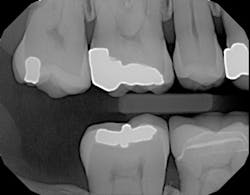

Here's another example of where a patient benefited from this technology's ability to accurately display interproximal caries.1 The patient needed a crown on tooth No. 3, and adjacent tooth No. 2 looked clean on a bitewing x-ray (figure 5).

Figure 5: Bitewing x-ray shows no indication of caries on tooth No. 2Before I began prepping for the crown, I used CariVu. On the images, I saw not only a crack on the tooth that was to be crowned, but also clear caries on the adjacent tooth (figure 6). During treatment, I snapped a picture of the preparation on tooth No. 2 with an SLR extraoral camera (figure 7). I took an additional photo mid-treatment to show how far the cavity had progressed into the dentin. The bitewing didn't show any of this decay. This caries detection technology gives me a great opportunity to tell patients that I found a cavity that we would not have known about until it caused trouble. There is no surprise later and no apologies for missing an early lesion.